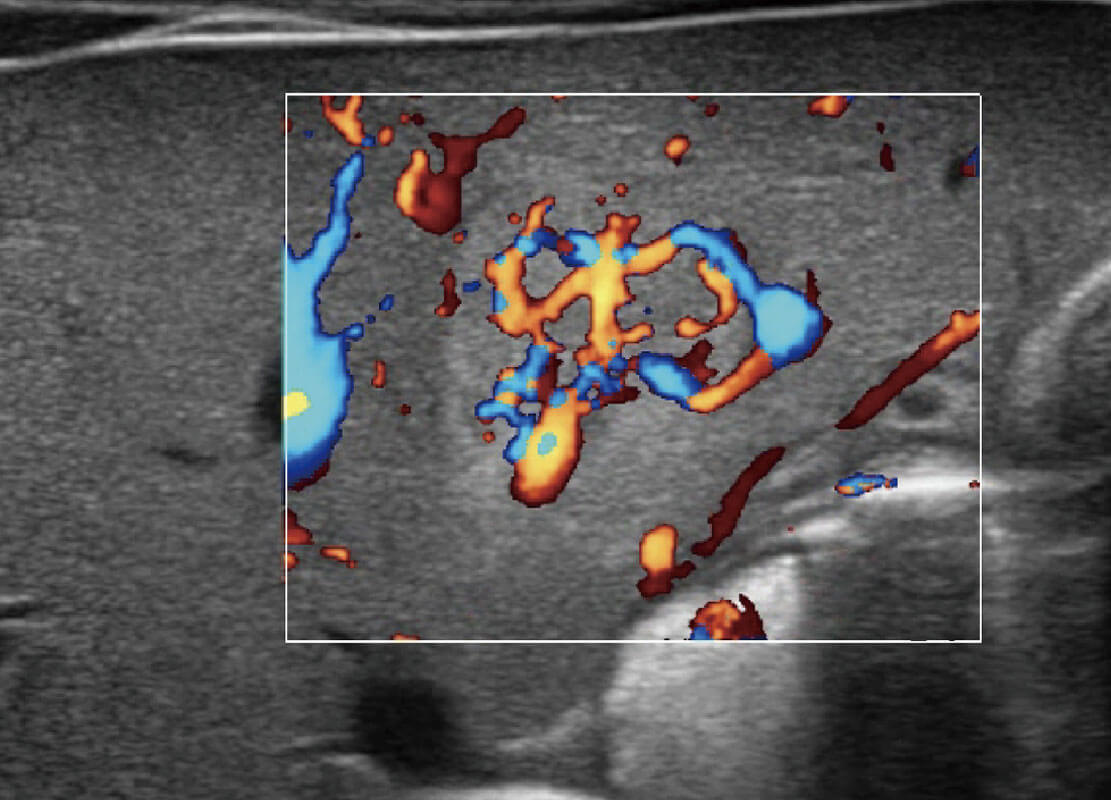

生殖健康

P60优异的图像质量搭载专科探头,在妇科基础疾病的诊断、卵泡生长的监测、输卵管通畅情况的判别等方面为您提供生殖应用方案。

乳腺超声 / 新生儿

P60搭载宽频带线阵探头、宽景成像、弹性成像技术,为您提供乳腺应用方案。P60支持高频相控阵探头、线阵探头、腹部高频探头、腹部微凸探头等,丰富的探头群搭载敏感的彩色血流成像,适用于新生儿多种脏器检测要求,满足新生儿筛查需求。

• 乳腺癌显微血流

• 新生儿肝血管癌